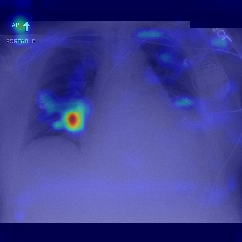

Fig.Β 5: Examples of class activation maps of positive cases. Left to right: image with annotation in blue, no L1 regularization, with L1 regularization, baseline.

Fig. 5 shows examples of class activation maps of positive cases for visual comparisons among the final models. These were produced using the Grad-CAM approach [14]. The images were annotated by an expert for the regions of opacity. Although all models correctly classified the cases as positives, the activation maps of the baseline model were barely correlated with the annotated regions, with more irrelevant hot spots outside the lungs. On the other hand, the activation maps of the models with feature selections were better correlated with the annotation. In other words, these smaller networks seems to be also more focused on the correct regions, which is a step towards explainability. The image in the third row shows that the VGG16 activation map has important components outside the lungs, focusing on English characters on the image. Whereas the reduced networks show more activation in marked areas of the lungs.